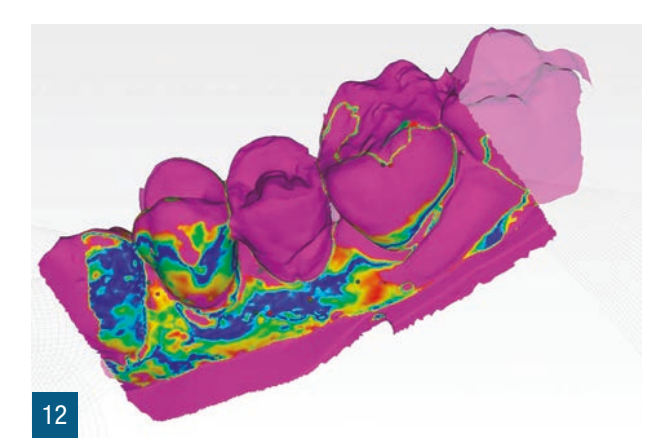

Пацієнтка 36 років звернулася до нас з частковим переломом коронки другого премоляра праворуч (1.5). Після перевірки неможливості консервативного відновлення було заплановано імплантно-протезне лікування з негайною екстракцією для заміни ураженого елемента (Рис. 1,2). Пацієнтка, не курець, була класифікована як ASA 1. Було виконано локалізовану CBCT в ураженій області для перевірки наявності та морфології вестибулярної кісткової стінки навколо елемента, що підлягає екстракції, в альвеолярному відростку. Перед екстракцією 1.5 була виконана цифрова внутрішньоротова відбитка (iTero Flex, Align Technology) зуба та прилеглих ділянок (Рис. 3). Після плескальної анестезії була виконана екстракція, обмежуючи травму пародонтальних тканин, розділяючи корені та використовуючи міні-важелі та синдесмотоми для збереження вестибулярної кісткової пластини. Оцінюючи цілісність альвеоли та сприятливі анатомічні умови, переходять до встановлення імплантату розмірів, що забезпечують адекватну первинну стабільність (4.1 x 11,5 TSVH ZimmerBiomet). Імплантат розміщується в близькій до піднебіння позиції відповідно до вказівок літератури (Рис. 6,7), заповнюючи проміжок між імплантатом та вестибулярною кістковою кортикою за допомогою гетерологічної кісткової пересадки (Copioss Zimmer-Biomet). Монтажний пристрій формують так, ніби це абатмент, і після його закручування на імплантаті проводять сканування. З цифрового внутрішньоротового сканування виконується CAD проектування гвинта загоєння (Рис. 4). У проекті буде використано як передекстраційне сканування, так і сканування з монтажним пристроєм, перетвореним в абатмент, щоб максимально точно відтворити гвинт загоєння. Морфологія гвинта загоєння відтворить існуючі тканинні умови на момент хірургії та дозволить уникнути естетичних дефектів у рожевій естетиці. Завершивши цифрове проектування, виконується 3D-друк з смоли (Lab2 Formlab) кастомізованого гвинта загоєння. Після завершення друку, отриманий гвинт загоєння з смоли Nextdent цементується з авто- та фото-твердим смолистим цементом (Relix Unicem, 3M) до абатмента, отриманого з монтажного пристрою, а потім закручується на імплантат (Рис. 5,6). Було проведено рентгенологічні контролі через три місяці та через рік (Рис. 7,8). Через 3 місяці була виготовлена остаточна коронка через цифровий потік з тим самим сканером та спеціальними сканбоді (Gentek, Zfx), які дозволяють ідентифікувати точне просторове положення імплантату. Через тиждень була передана остаточна монолітна коронка з фарбованої цирконії, закручена на ti-base (Рис. 9,10). Через рік було виконано ще одне сканування для оцінки з часом можливих об'ємних змін періімплантних тканин. Сканування, виконані на етапі передекстракції та через рік, були оброблені за допомогою спеціалізованого програмного забезпечення (meshlab) для оцінки розмірних змін (Рис.11-13).

У зв'язку з клінічними цілями, описаними Тарновим та співавторами, з цього клінічного випадку видно, як одночасна стабілізація кісткового сайту та заповнення існуючого зазору гетерологічним матеріалом дозволяє зберегти горизонтальні та вертикальні об'єми постекстракційного сайту. Швидкість і легкість виконання кастомізованого загоювального гвинта за цією методикою дозволяє покращити герметичність трансмукозного шляху та зберегти морфологічні та об'ємні характеристики до екстракції. Якщо використовувати неанатомічні загоювальні гвинти більшого діаметра, ми, безумовно, отримаємо кращу герметичність у порівнянні з класичними стандартними загоювальними гвинтами, але вони не дозволять точно відтворити межі постекстракційного сайту, як кастомізований загоювальний гвинт, отриманий за аналоговою та/або цифровою методикою. Цифровізація дозволяє суттєво скоротити час виконання та забезпечити більшу персоналізацію отриманого виробу. Точне відтворення існуючої ситуації, ймовірно, може гарантувати імпланту меншу кількість обслуговуючих втручань, таких як закручування та відкручування, на етапах проби. Цей клінічний випадок пропонує, як стабілізація періімплантних тканин може забезпечити оптимальне загоєння та зрілість тканин, спрощуючи фінальні етапи протезування. Це може дозволити уникнути подальших втручань для управління періімплантними тканинами, таких як повторні хірургії, пересадки та використання тимчасових конструкцій. Етап CAD дозволяє точно відтворити профільEmergence, копіюючи форму шийки зуба. Крім того, слід врахувати, що аналогове виготовлення загоювального гвинта вимагає простоїв, які можна використовувати для інших цілей, і тому в управлінні під час операції прискорюється робочий процес і досягнення кінцевого результату. Використання цифрових сканувань до та після хірургії дозволило порівняти об'єми періімплантних тканин, накладаючи сканування до та після хірургії через три місяці та через рік, щоб виявити об'ємні зміни. Це корисний інструмент для можливих клінічних оцінок, а також для комунікації з пацієнтом.